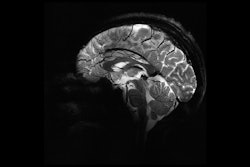

Q Bio has launched Tensor Field Mapping (TFM), a multiparametric MRI quantification software application.

TFM enables tissue properties to be measured and benchmarked on MRI on an ongoing basis, according to Q Bio. This data can be shared, pooled, and compared, regardless of scanner type and clinical settings. AI software will also immediately be able to access the harmonized, quantitative data in order to accelerate diagnostics, the firm said.